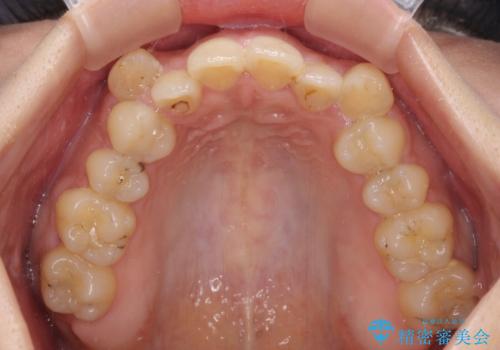

- 八重歯と上下前歯のでこぼこを気にして来院された患者様です。

上下前歯部叢生のスペース獲得のため、上下顎左右小臼歯各1歯(計4本)と全ての親知らずを抜歯して、矯正治療を行うこととしました。